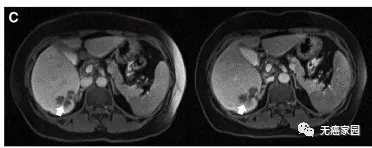

典型病例示意图

通过MRI观察到患者P10的一个肝脏病变发生萎缩